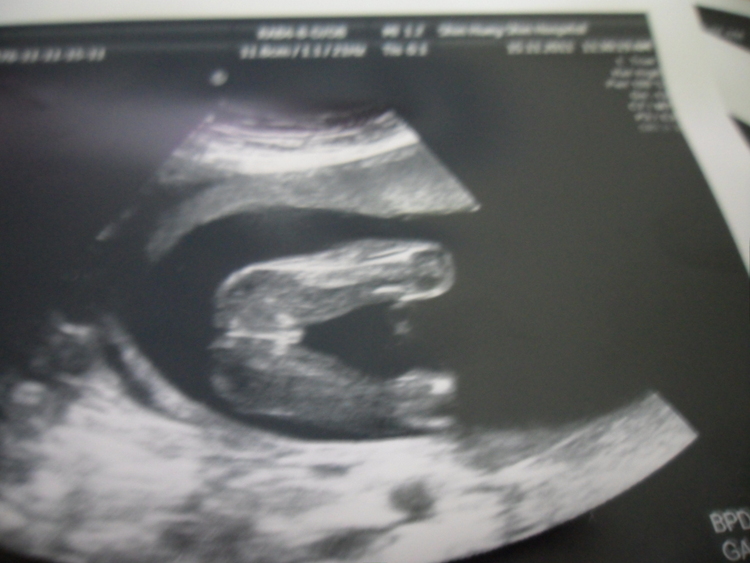

我目前懷孕19週六天..之前去照都因為位置關係所以照不到性別..今天去照超音波醫生說是女生...請問這樣就真的確定是女生了嗎??請有經驗的媽咪幫我看一下..謝謝喔^^

寶寶的腳開很大特徵也很明顯,應該是妹妹沒錯!!

我家小龍女當初雙腳開的角度還不到板水家寶寶的1/2咧!!